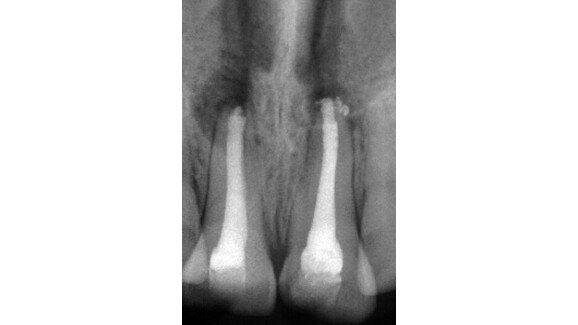

When the patient was referred to our department, extra- and intra-oral examinations (including radiology) were performed through which it was established that the left and right maxillary central incisors were in normal position with enamel–dentine fracture. The root canals were wide, the roots incompletely formed with open apices and there were periapical lesions (Fig. 1). Cleaning and shaping of the root canal system was achieved under rubber dam isolation. The solution used for irrigation was 2.5% sodium hypochlorite. Root canal length was determined using an apex locator and confirmed radiographically. Ca(OH)2 paste was placed in the canals for one week for disinfection. During the second appointment, Ca(OH)2 was removed by mechanical instrumentation and flushed from the root canals by means of sterile water irrigation. The canals were dried using sterile paper points. MTA was prepared immediately before use, placed into the canals with an MTA carrier and compacted with a hand plugger to create an apical plug of 3 to 4mm in accordance with the manufacturer’s instructions. A radiograph was taken to check whether any apical extrusion had occurred.

The apical plug failed in the first attempt on the right maxillary central incisor (Fig. 2). The MTA was rinsed out with sterile water and the procedure was repeated (Fig. 3). Moist paper points were placed in the canals and the access cavities were closed with a temporary restorative material, IRM (DENTSPLY).